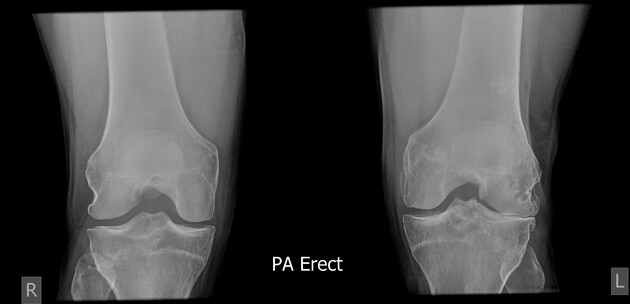

골관절염 (osteoarthritis)

- 좌측 관절이 우측에 비해 더 좁다.